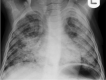

Tuberculosis (TB) remains one of the major public health threats worldwide, despite improved diagnostic and therapeutic methods. Tuberculosis is one of the main causes of infectious disease in the chest and is associated with substantial morbidity and mortality in paediatric populations, particularly in low- and middle-income countries. Due to the difficulty in obtaining microbiological confirmation of pulmonary TB in children, diagnosis often relies on a combination of clinical and radiological findings. The early diagnosis of central nervous system TB is challenging with presumptive diagnosis heavily reliant on imaging. Brain infection can present as a diffuse exudative basal leptomeningitis or as localised disease (tuberculoma, abscess, cerebritis). Spinal TB may present as radiculomyelitis, spinal tuberculoma or abscess or epidural phlegmon. Musculoskeletal manifestation accounts for 10% of extrapulmonary presentations but is easily overlooked with its insidious clinical course and non-specific imaging findings. Common musculoskeletal manifestations of TB include spondylitis, arthritis and osteomyelitis, while tenosynovitis and bursitis are less common. Abdominal TB presents with a triad of pain, fever and weight loss. Abdominal TB may occur in various forms, as tuberculous lymphadenopathy or peritoneal, gastrointestinal or visceral TB. Chest radiographs should be performed, as approximately 15% to 25% of children with abdominal TB have concomitant pulmonary infection. Urogenital TB is rare in children. This article will review the classic radiological findings in childhood TB in each of the major systems in order of clinical prevalence, namely chest, central nervous system, spine, musculoskeletal, abdomen and genitourinary system.